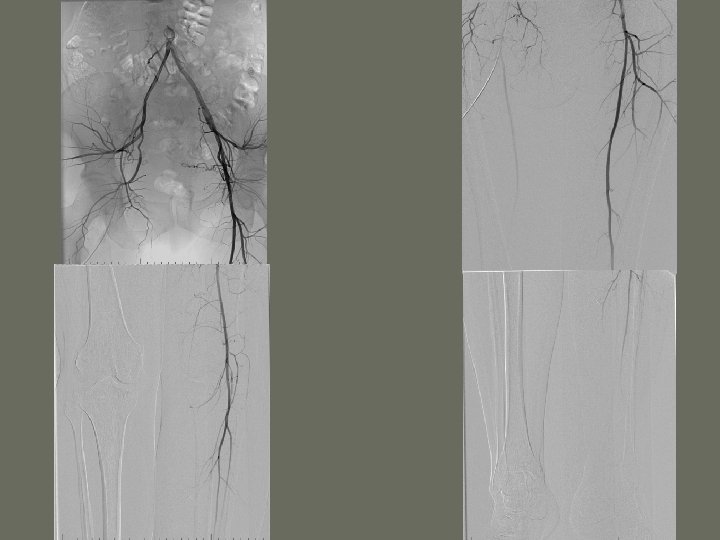

General Angiography Procedures 5. Peripheral Angiography • radiographic study of the vessels of the upper or lower limbs following the injection of contrast medium • Abdominal Aortography with _______

General Angiography: Peripheral Venography • radiographic study of the _____ veins from the ankle to the pelvic area, or the wrist to the shoulder • frequency declining due to vascular sonography (Doppler)